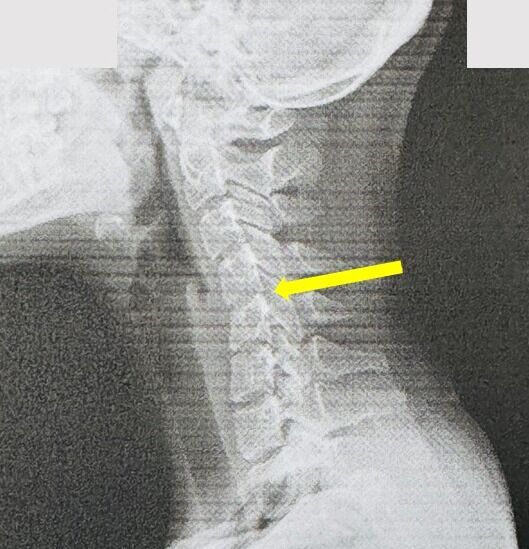

這張X光片,無聲地訴說著一個可怕的事實。健康的頸椎,從側面看,天生就帶有一個優美的「C字形」向前弧度。這個弧度是上帝賜予的天然避震器,用來支撐頭顱的重量、緩衝日常活動的壓力。然而,請看左圖這位20歲女孩的頸椎,那條生命曲線已經消失,變成一條令人擔憂的僵硬直線!這就是「手機頸」或「軍人頸」,是頸椎結構提早退化的鐵證。

圖片說明:X 光片顯示,該患者的頸椎排列不正常,且椎間盤高度明顯降低,甚至出現輕微骨刺增生